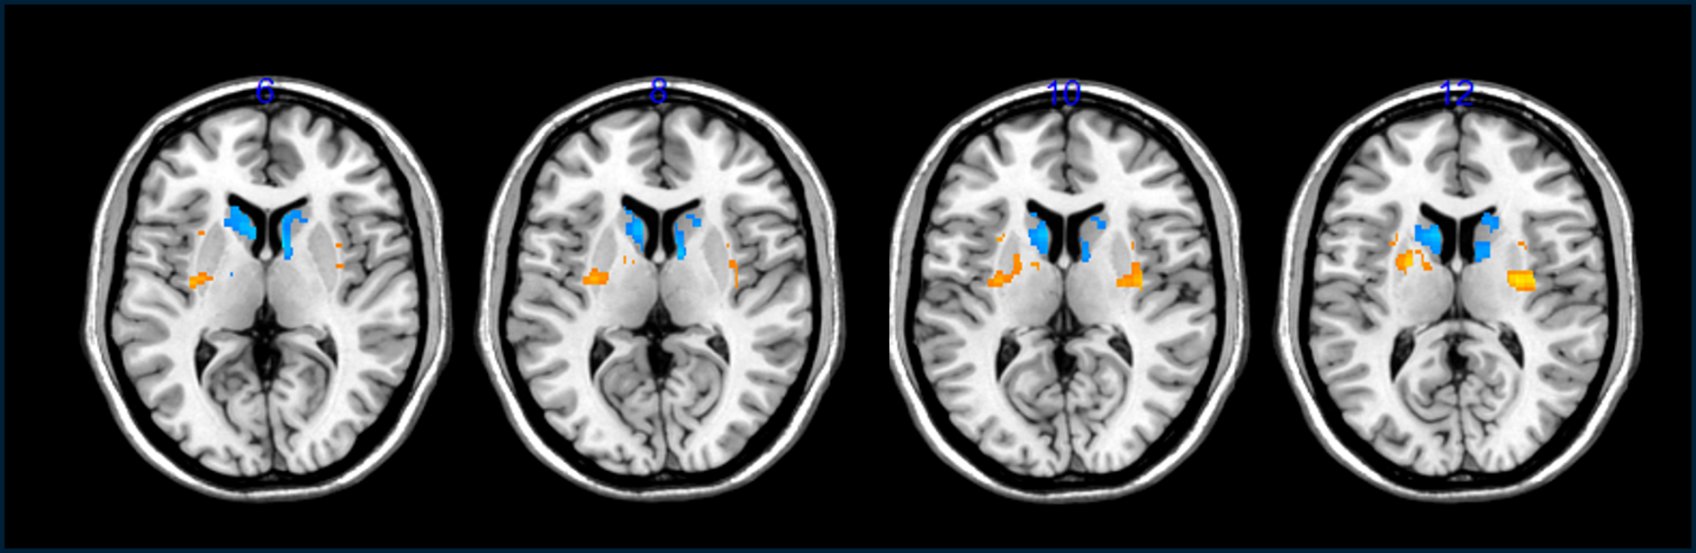

从显示病人大脑中多巴胺细胞增加的脑部扫描以及“关闭时间”(或者患者因症状而感到无法活动的每日小时数)减少的情况来看,移植手术似乎有所帮助。

因为研究者无法直接看到植入人脑的细胞,他们通过给患者注射多巴胺的放射性前体,并在PET扫描中观察其在大脑中的摄取来跟踪这些细胞的存在。对于Barker来说,这些结果并不那么令人信服,他说现在“仍然为时过早”来判断移植的细胞是否已经植入并修复了患者的大脑。